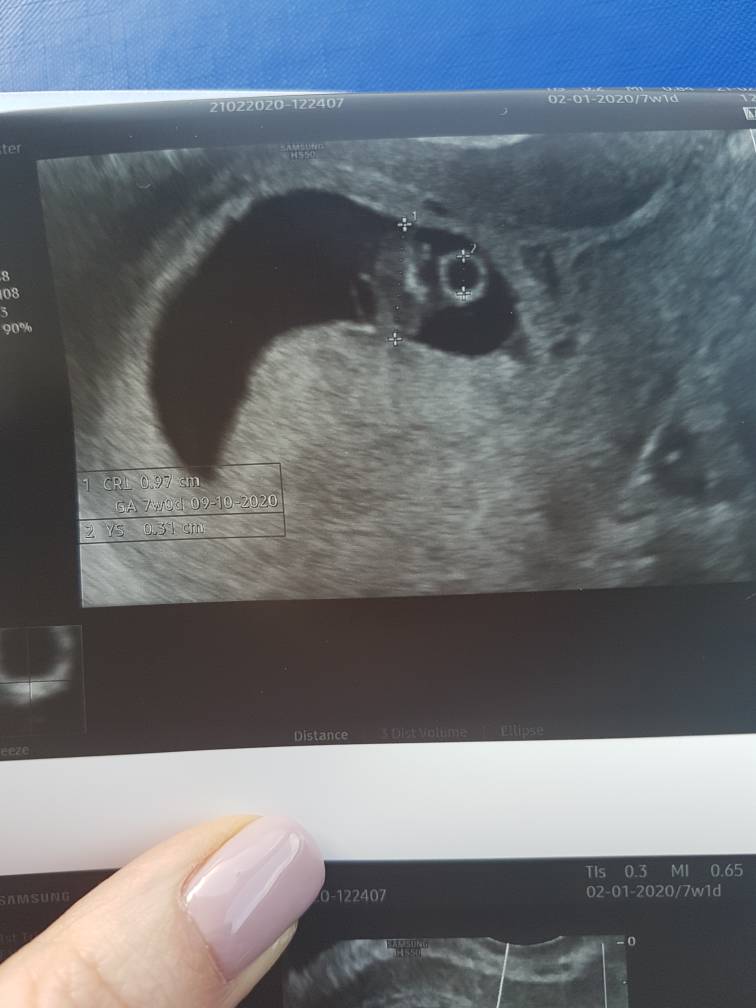

Kropus jest i ma się dobrze [emoji7][emoji7][emoji7] gorzej z jego matką, bo ciągle jeszcze popłakuje. Kropus dobrych wymiarów, pęcherzyk zoltkowy z którego czerpie energię również prawidłowych wielkości. Serduszko bije prawidłowo 131. Nawet je slyszelismy

@bazylia128 prosze o dopisanie do kalendarza 03.03 wizyta w klinice i 30.03 badania prenatalne. A o i jeszcze mi powiedział, ze w zwiazku z tym,ze nie miałam toxo to mam uważać, zero kontaktu z kotami i dochodami i muszę ja zbadać w 20 i 30 tyg ciazy i tego pilnować. A na koniec pokazuje Wam nasz CUD[emoji173] i dalej wyje.